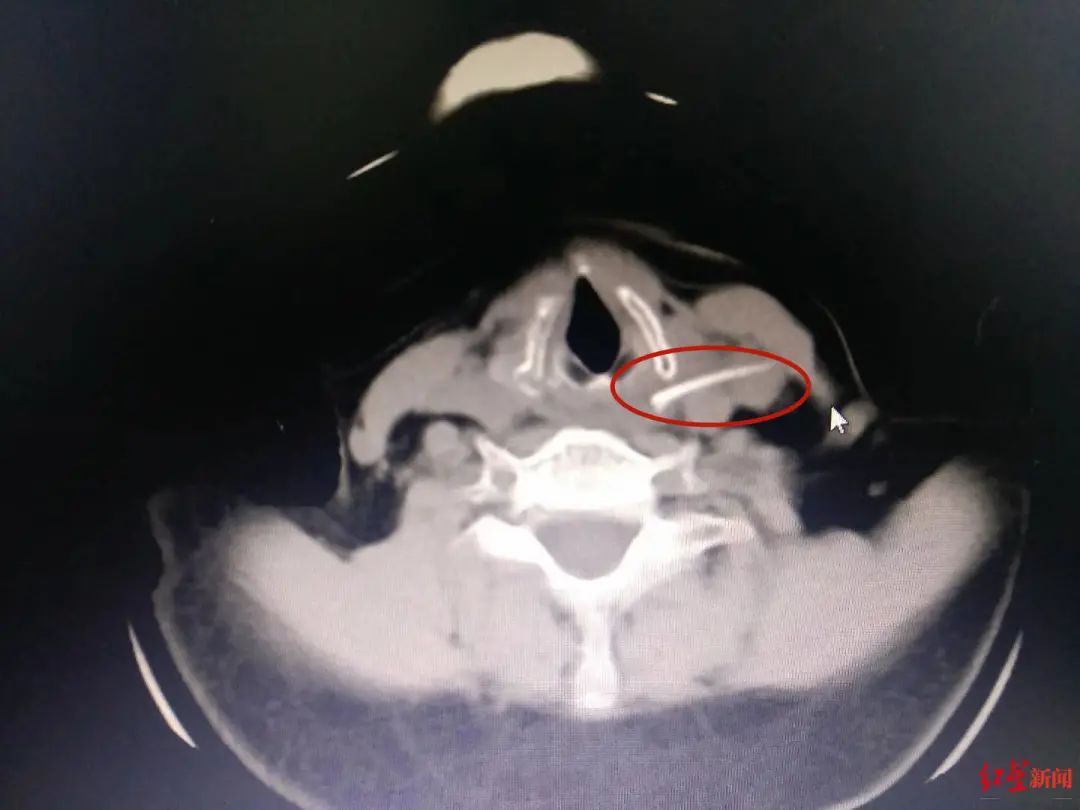

赵小龙说,在急诊科,急诊医生通过CT发现,鱼刺已经从颈总动脉的表面穿入颈内静脉的中间,“这是颈部非常重要的两根血管,一旦穿破,将危及生命。”随后,患者被紧急送到耳鼻咽喉头颈外科,并在全麻状态下进行手术。

手术最大的难题是找到这根隐蔽的鱼刺。为此,医生在结合食道镜、X光、超声、CT等检查结果后,采取了颈外侧切口取刺的办法。“颈总动脉的特点是出血量大,而且迅速。加之受到炎症的刺激和周围组织粘连,稍有不慎极易破裂,引发生命危险。”赵小龙说,手术中每一步操作都如履薄冰,最终团队历时4个多小时,深夜11点左右顺利将3厘米左右的鱼刺取出。